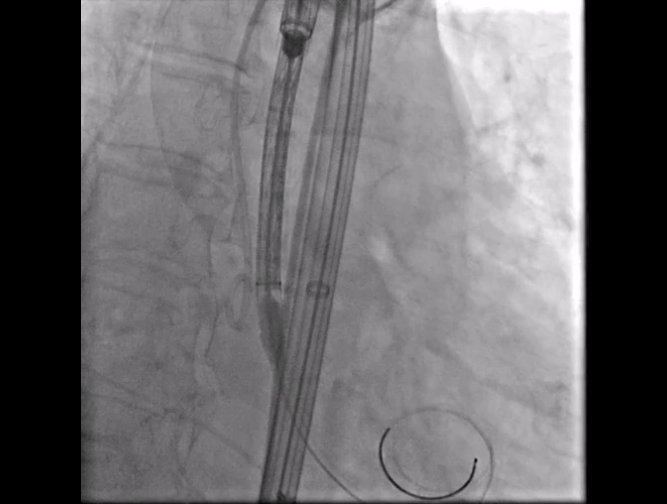

Step 4.输送系统进入:过弓性能优异,悬空通过,整体过程未将鞘管顶起至弓顶部

过弓示意图